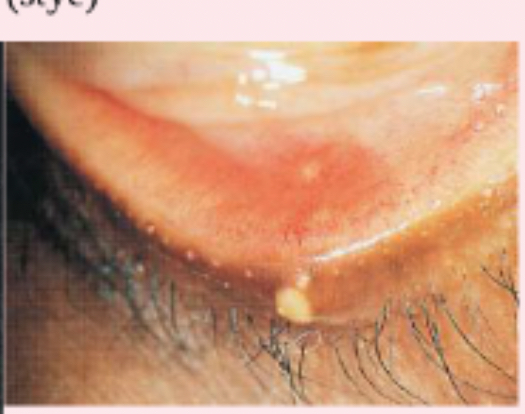

hordeolum (stye)

entropion